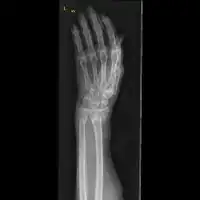

| Midshaft fracture of the radius and ulna | |

Front view of displaced fractured radius and ulna at wrist